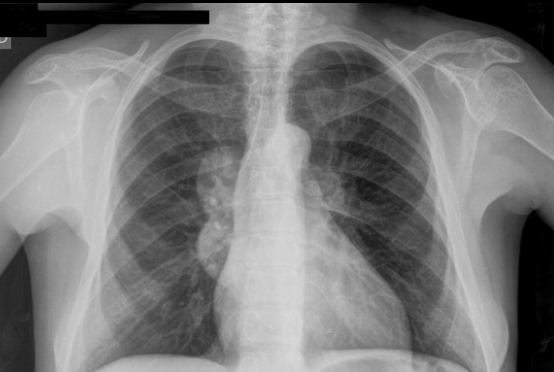

Ground glass opacification

1. Pulmonary oedema

2. Pulmonary haemorrhage

3. Atypical infection (PCP, CMV)

4. ARDS

ARDs vs pulmonary oedema: normal size heart and no pleural effusion in ARDS